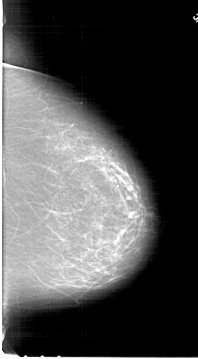

A_1778_1.LEFT_MLO

LEFT_MLO LINES 6871 PIXELS_PER_LINE 3661 BITS_PER_PIXEL 12 RESOLUTION 43.5 OVERLAY